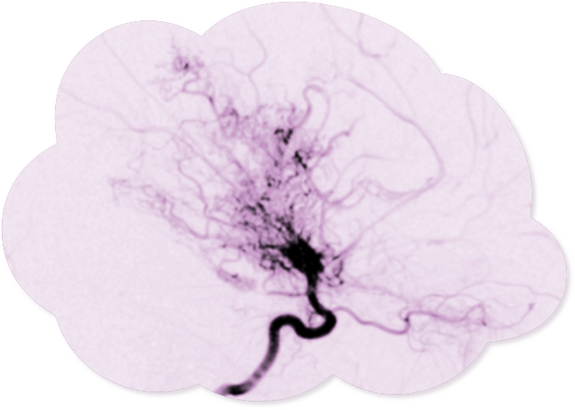

Natural Compensation

The brain tries to compensate for the disturbed circulation by developing fragile and small arterial collaterals. In reference to the shape of these bypassing circuits, the Japanese neurosurgeons J. Takeuchi and K. Shimizu, who first described the symptom in 1957, named the disease Moyamoya - Japanese for "little cloud" or "puff of smoke".

The first step is usually an intensive evaluation by a pediatric neurologist. The patient's brain is scanned with MRI and blood flow is measured with a PET scan. This is followed by an in-depth examination of the brain arteries with an angiogram.